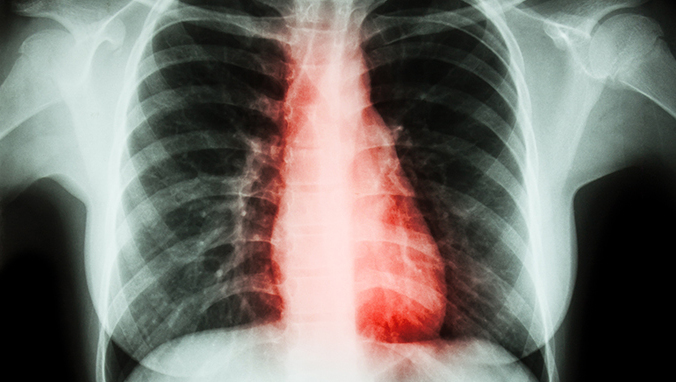

肺癌脑膜转移的生存期

说实话,肺癌脑转移是最难治疗的转移癌之一;肺癌脑转移后的生存期取决于转移被发现的时间早晚、转移灶的大小和数量、孤立病灶是否处于要害部位、有无明显症状和体征、与原发肺癌的发病间隔时间以及有无其他部位的转移等因素,并不能一概而论,每个人的情况都不一样。整体上讲,发生脑转移后患者的自然生存时间大约是1-3个月且大多数患者都会伴有颅内高压症状及肢体、语言障碍等,脑转移一旦发生病情会进展迅速,预后不良。